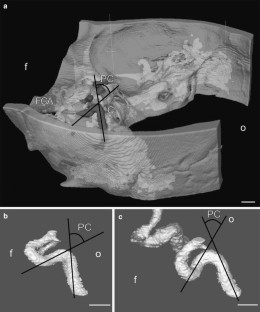

Three-dimensional (3D) computer models, reconstructed from contrast enhanced computed tomography (CT) data of 30 randomly selected patients (60 pICAs) were analyzed with modern visualization software and new mathematical algorithms. As objective measures for the pICA shape complexity, we provide calculations of curvature energy, torsion energy, and total complexity of 3D skeletons of the pICA lumen. We further measured the posterior knee of the so-called “carotid siphon” with a virtual goniometer and performed correlations between the objective mathematical calculations and the subjective angle measurements.

Firstly, our study provides mathematical characterizations of the pICA shape, which can serve as objective reference data for analyzing connections between pICA shape complexity and vascular diseases. Secondly, we provide an objective method for creating such data. Thirdly, we evaluate the usefulness of subjective goniometric measurements of the angle of the posterior knee of the carotid siphon.